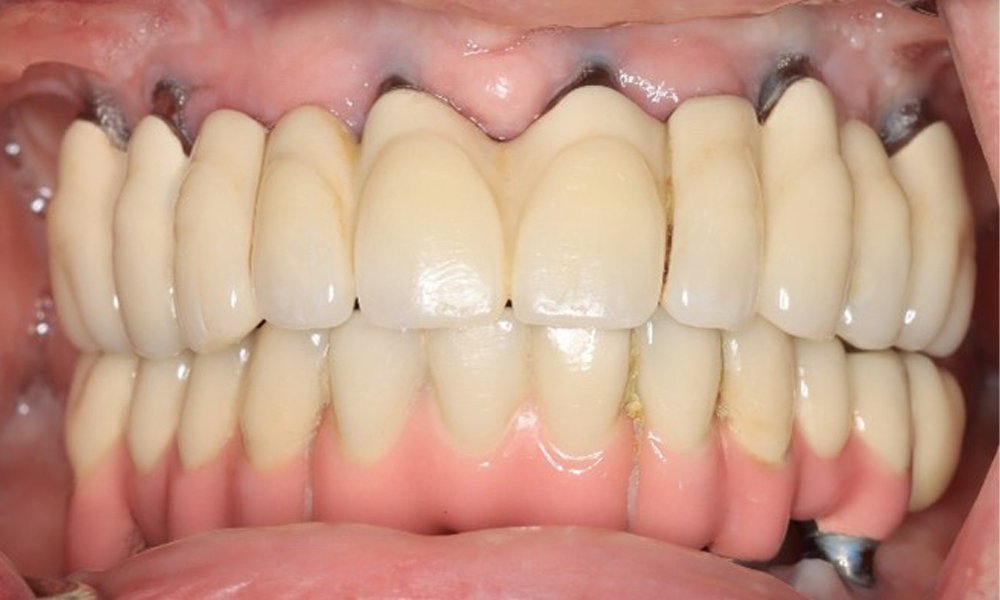

Преден изглед на зъбите (горна и долна челюст)

Фигура 3: Фронтален изглед